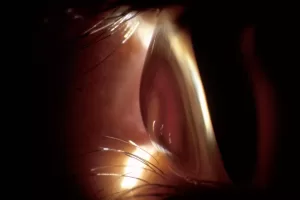

لیزیک چگونه کار می کند

لیزیک قرنیه، سطح شفاف و گرد چشم را تغییر شکل می دهد، بنابراین نوری که وارد چشم می شود را بهتر متمرکز می کند. کره چشم توسط یک حلقه مکش در جای خود نگه داشته می شود و قرنیه بلند شده و صاف می شود. جراح یک فلپ کوچک و لولایی در قرنیه ایجاد می کند و آن را به عقب تا می کند. سپس یک لیزر اگزایمر – یک پرتو نور فرابنفش – قرنیه را بر اساس معاینه چشمی که قبل از جراحی انجام دادهاید، تغییر شکل میدهد. فلپ قرنیه به جای خود تا می شود.